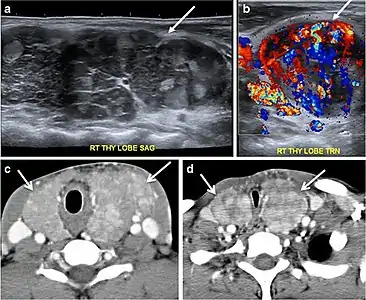

Fig. 3. An incidental PTC in a 62-year-old male patient with lymphoma. a, b Enhanced axial CT scan and fused PET/CT scan of the neck demonstrate a well-defined, hypodense right thyroid nodule (white arrow) with high FDG uptake. The FDG-avid uptake in the left side (circle) is related to patient's known lymphoma, which resolved after treatment. c, d Transverse greyscale and sagittal colour Doppler ultrasound of the neck demonstrate a right thyroid irregular hypoechoic lesion with some micro-calcifications (white arrows) and increased vascularity.[1]

On CT scans, a malignant lesion is suspected when the margins are ill-defined and there is extra-thyroid extension, lymph node involvement, or invasion of the surrounding structures. The absence of these features does not exclude malignant tumours, especially papillary, follicular, and medullary thyroid carcinomas (Fig. 3). Therefore, ultrasound is the modality of choice for thyroid lesion evaluation, due to its superior spatial resolution compared to CT examinations. Sonographic features of malignancy are micro-calcifications, acoustic shadowing, anti-parallel orientation, marked hypoechogenicity, irregular or microlobulated margins, and increased vascularity. CT scans lack the ability to detect these reliable sonographic signs of malignancy. Therefore, further management of ITNs, if required, usually begins with thyroid ultrasound and FNA should be considered according to the ultrasound findings.[1]